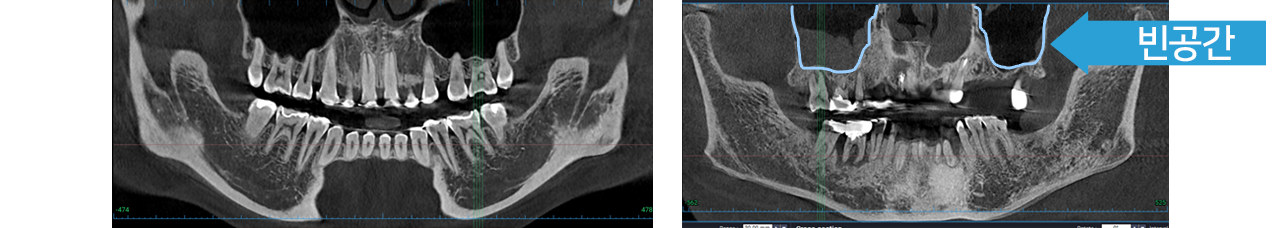

상악동 비교

뼈이식

단단하고 넓은 아래턱의 잇몸뼈와는 다르게 위턱

잇몸뼈는 비어있어 일반적으로 잇몸뼈가 부족할 때가

많습니다.

상악동은 사람마다 위치나 크기가 다릅니다.